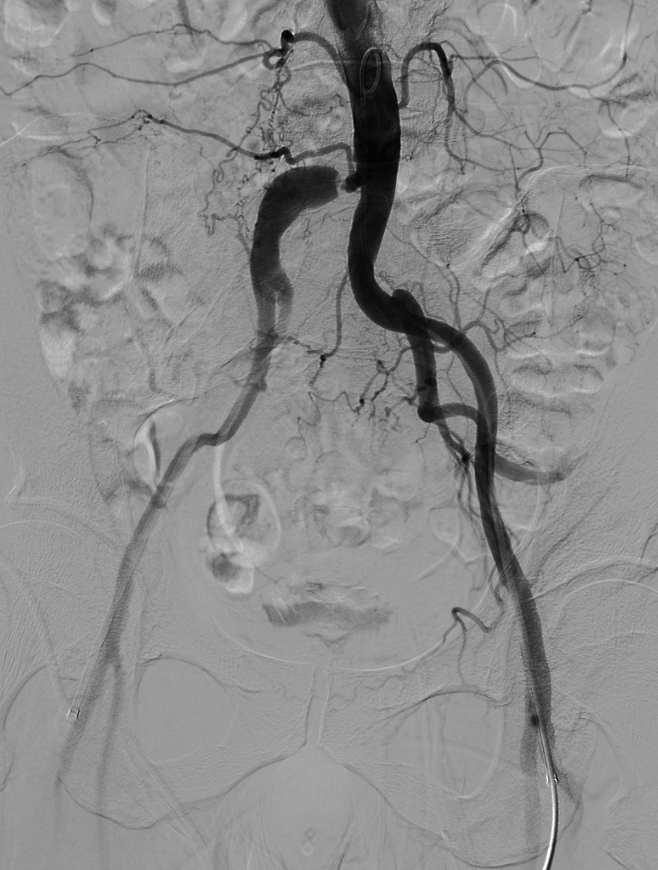

(2)泥鳅导丝配合PIGTAIL导管进入腹主动脉,行主髂动脉造影显示:右侧髂总动脉重度狭窄,走行迂曲,后伴狭窄后扩张;双侧髂内、髂外动脉显影正常。

导丝怎么扩【问术ASK】佟铸教授:双侧髂总动脉“对吻”球扩覆膜支架植入术_https://www.jmylbn.com_新闻资讯_第4张

(4)延双侧加硬泥鳅导丝进入LifeStream 10*38mm球扩覆膜支架,再次经双侧长鞘同时造影,明确病变及支架释放位置。

导丝怎么扩【问术ASK】佟铸教授:双侧髂总动脉“对吻”球扩覆膜支架植入术_https://www.jmylbn.com_新闻资讯_第6张